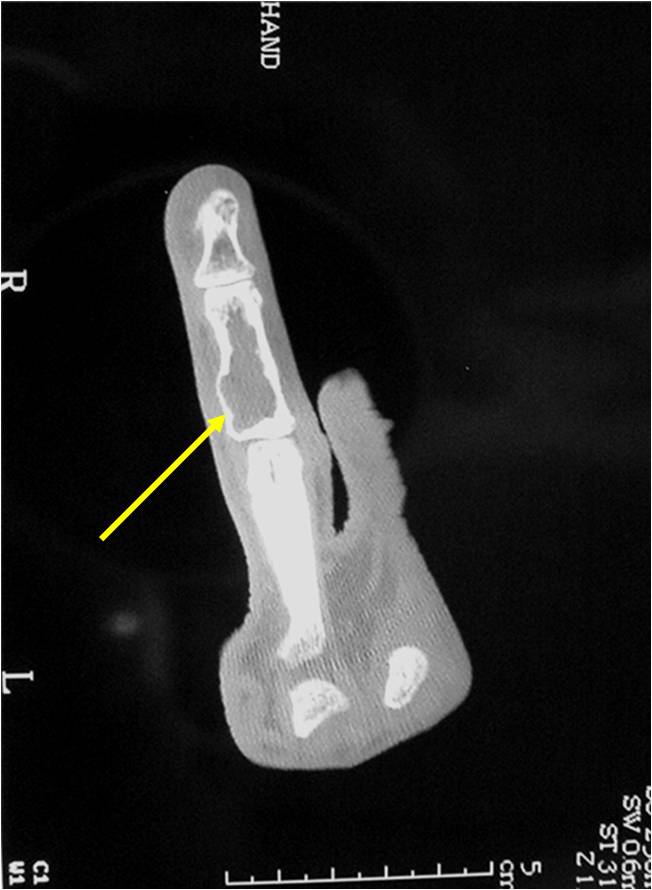

- Localized, radiolucent defect usually with punctate calcifications

- Calcifications are typical but not always present

- Matrix may demonstrate various degrees of calcification

- Calcifications are stippled, punctate, popcorn like calcifications and “Ring and Arc” calcifications

- Cartilage tumors grow in a lobular manner. The perimeters of the lobules undergo

- enchondral ossification that may calcify. If the entire perimeter of the lobule calcifies it appears

- radiographically as a “Ring”. If a portion of the perimeter of a lobule calcifies it forms an “Arc” on

- an X-ray.

- May be located centrally or eccentrically

- Grows eccentrically or concentrically (phalanges)

- Cortex may be scalloped and thinned in the phalanges

Plain X-Ray:

- Geographic lytic lesion

- Central often metaphyseal in long bones

- Can be eccentric also

- Expansile remodeling with thinned cortex

- Chondroid matrix with calcifications in majority of tumors

- Approximately 20% have limited or no calcifications